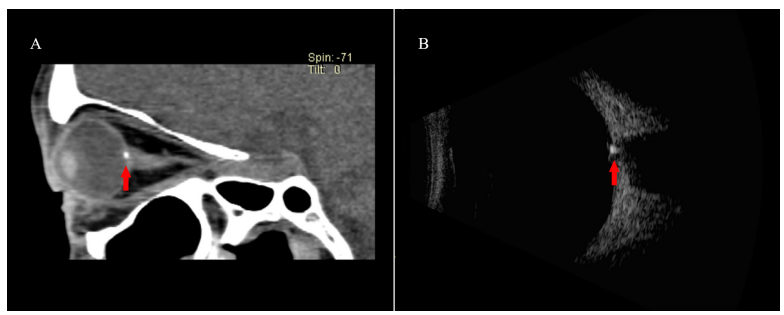

图 6 一例 ODD 的 CT 和超声影像

Figure 6 Orbital CT and ultrasound images of ODD.

ODD 患者眼眶 CT 可见点状高密度影 ( 图 A,红色箭头 );眼球超声可见眼球后壁视乳头 ( 视盘 ) 前强回声的圆形结构( 图 B,红色箭头 )。

A hypertensive dot (figure A, red arrow) was identifiable in the orbital CT of a patient with ODD, and a round hyperechoic structure (figure B, red arrow) of optic disc on the posterior wall of the eyeball was observed in the ultrasound.